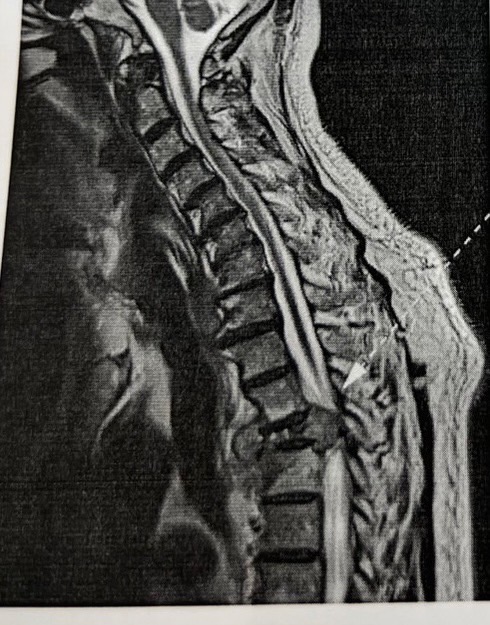

เมื่อต้นเดือนพ่อรู้สึกขาไม่ค่อยมีแรง ต้องใช้ไม้พยุง และหลังจากไปหาหมอ ตรวจโดยเข้าสแกน mri ผลออกมาแล้วพบก้อนในปอด

และก้อนที่กระดูกสันหลังทันเส้นประสาทใหญ่พอสมควร ทางรพ.จึงรีบส่งไปที่ศูนย์มะเร็งของจังหวัด

*ทางศูนย์มะเร็งเห็นผลตรวจ เลยให้ฉายแสงทันที 10 วัน และหมอแจ้งว่าเป็นมะเร็งระยะที่ 4 แล้ว และลามไปกระดูกสันหลัง

ลุกลามไปจุดอื่นด้วย โดยยังไม่ได้เจาะก้อนเนื้อตรวจ และมีนัด CT Scan อีกทีหลังฉายแสงค่ะ

ขอแนบรูปก้อนเนื้อที่พบนะคะ